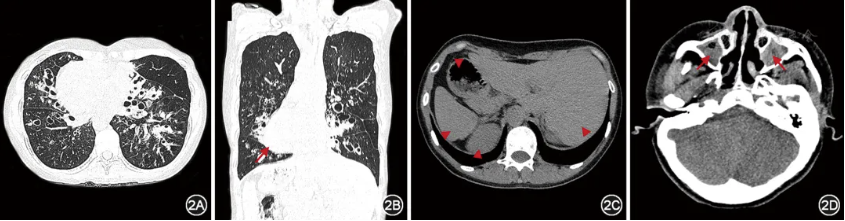

纤毛功能障碍累及多个器官,影像学检查应重点关注肺部、鼻窦、心脏和腹腔脏器等器官的表现。几乎所有的成人PCD胸部高分辨率CT(high resolution CT,HRCT)均显示出一定程度的支扩[13],病变主要分布在右中叶和左舌叶,其次为下叶,而上叶较少受累(图2)[13,32,35]。肺部的其他影像学特征还包括肺叶或肺段不张、黏液栓塞等,一般较少出现肺气肿和肺大疱。鼻窦CT可评估PCD患者是否存在鼻窦炎或鼻息肉。超声检查是评估心脏和腹腔脏器常用的检测手段,有助于评估PCD患者的内脏位置及是否合并先天性心脏病[17,36]。内脏位置的评估与判断对于患者以后可能的急性创伤评估或急诊手术时内脏器官的定位具有重要参考意义。

图2 典型原发性纤毛运动障碍患者CT所见 患者女,28岁,DNAH5双等位致病变异,胸部CT示右肺中叶、左舌叶及双肺下叶多发囊状支气管扩张,伴部分支气管管壁增厚、黏液栓塞,可见全内脏反位,长箭头示右位心,三角箭头示腹腔内脏全反位(胃、肝脏、脾脏、肾脏)(图2A~2C);鼻窦CT示双侧上颌窦黏膜增厚,窦腔见软组织密度灶填充,红色箭头示慢性鼻窦炎(图2D)